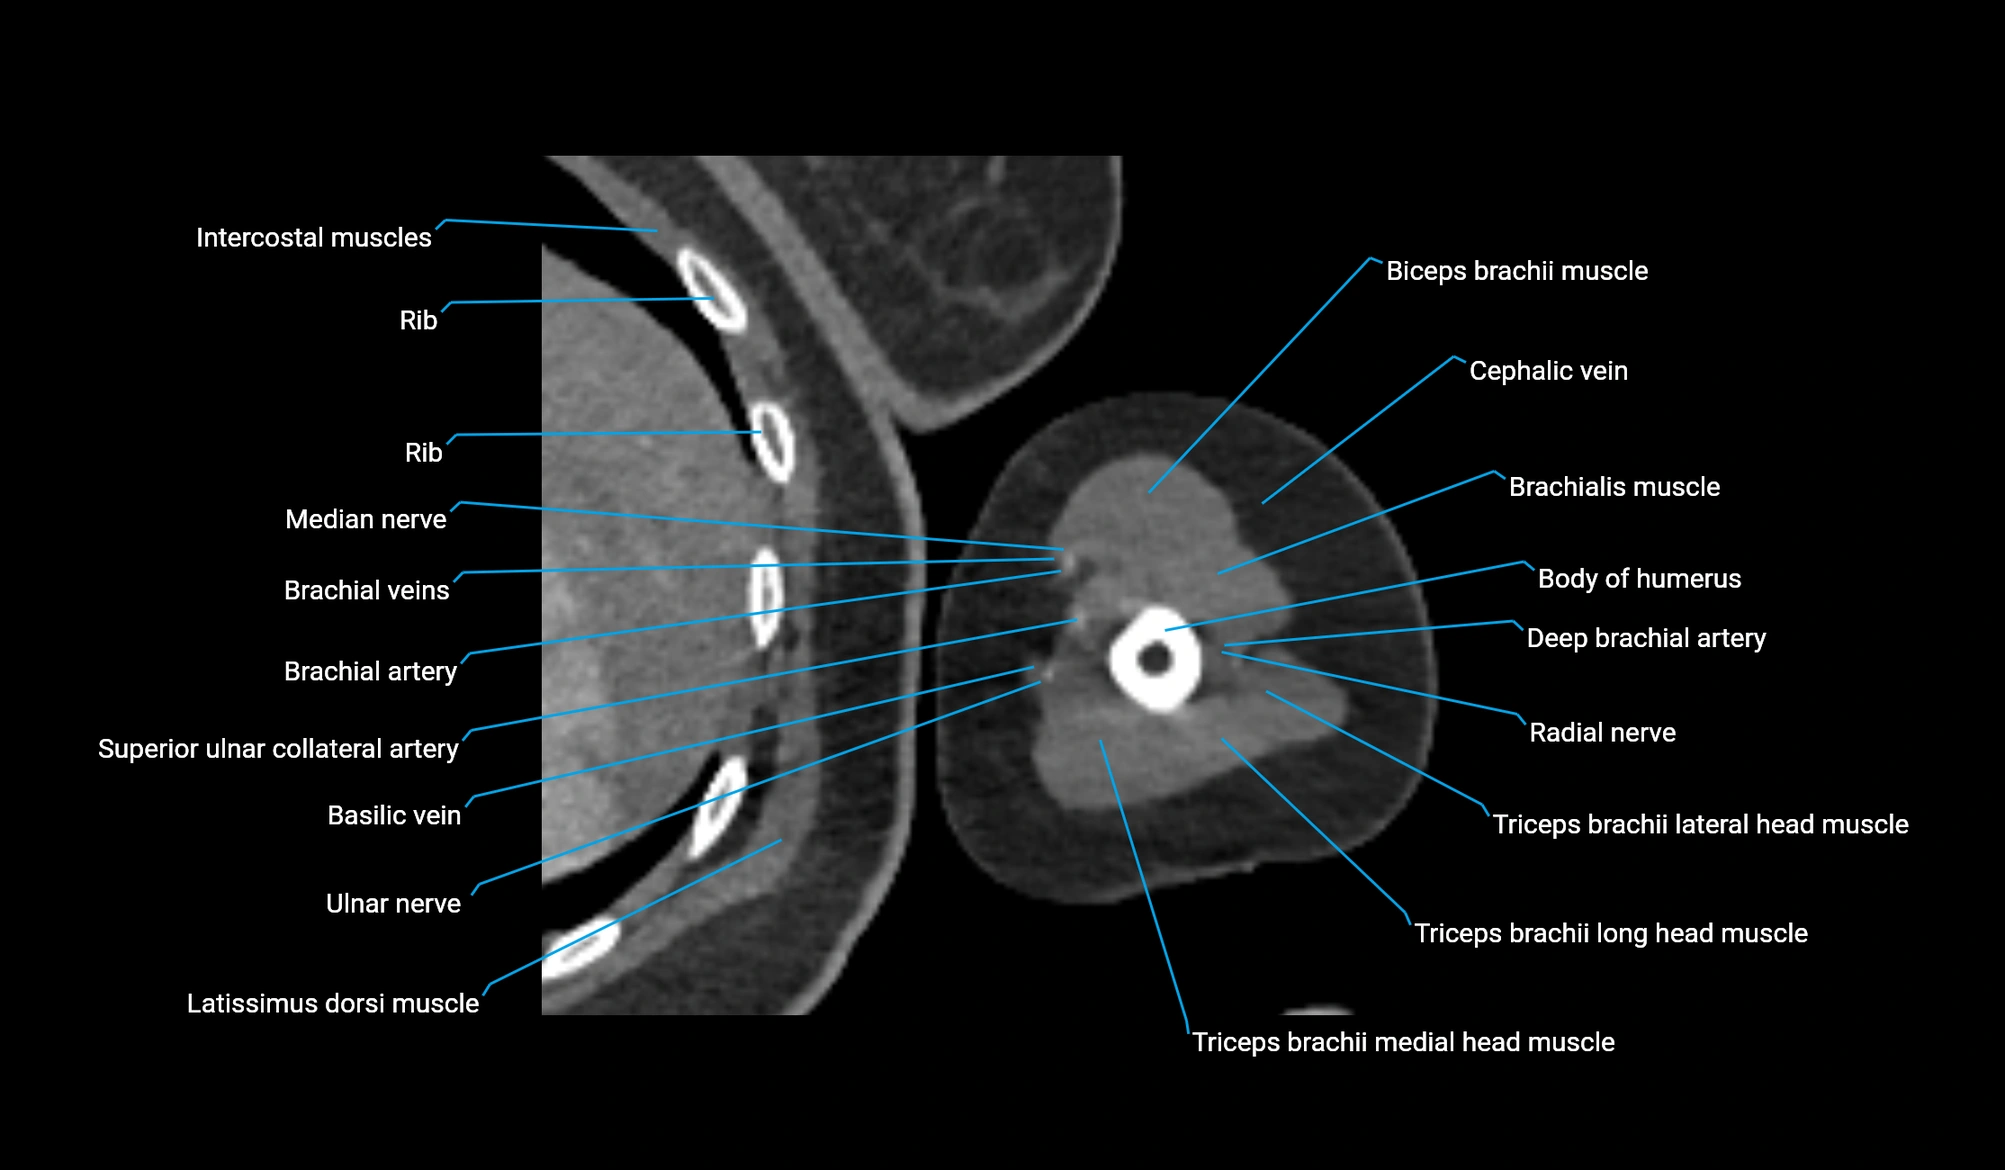

CT image